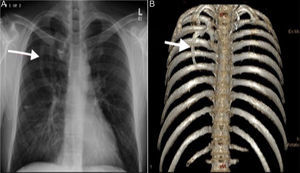

Intrathoracic rib (IR) is a very rare congenital anomaly resulting from incomplete fusion of neighboring sclerotomes.1 Three types have been defined in the literature. An extra rib originating from the vertebral body or proximal rib, defined as type 1A and 1B respectively. Type 2 is a bifid rib originating from a distal rib. A rib depressed in the thoracic cavity is type 3.2 Type 1A, an accessory rib originating from the vertebral body, generally descends vertically. The vertical course of Type 1A is associated with permanent lower lobe collapse and could be mistaken for a mediastinal or paravertebral mass.2 A middle aged man presented to our hospital with cough and chills. Frontal chest radiograph showed a vertically oriented right-sided linear density extending from the center of the chest inferomedially (Fig. 1A). Computed tomography study showed an intrathoracic rib originating from the inferiomedial part of the third rib, and 3D volume rendering technique showed the span of the extra rib in detail showing a type 1B IR (Fig. 1B). Although suggested in the literature as the best possible method to classify intrathoracic rib,1 we believe a computed tomography study is redundant in the digital radiography era, except for type 1A.